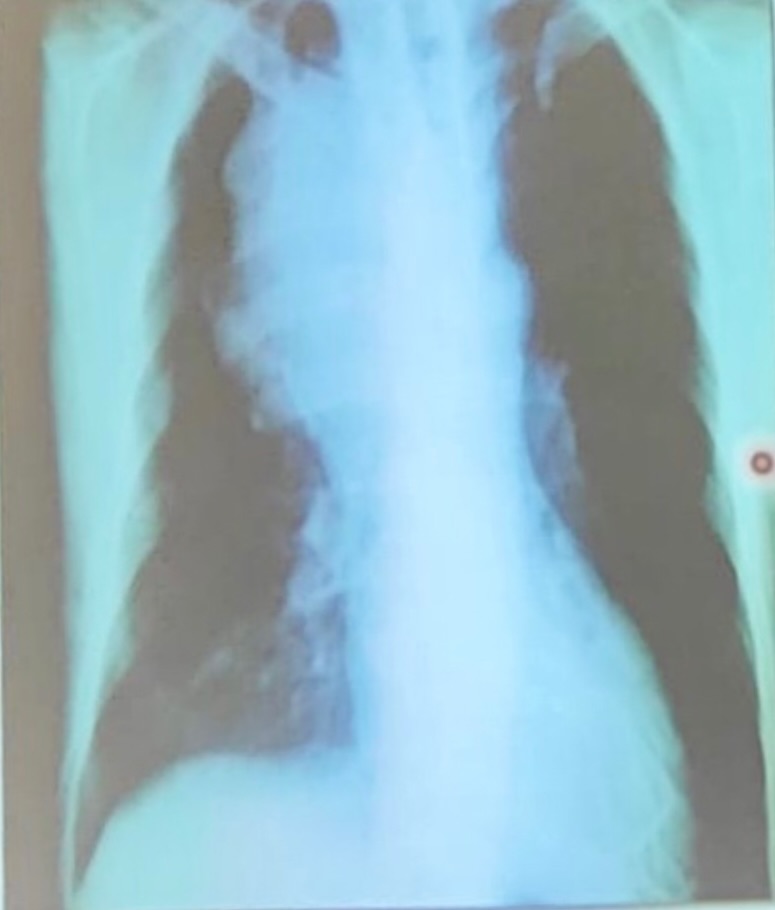

hidroneumotorax

enfisema sub-cutaneo mas derrame pleural